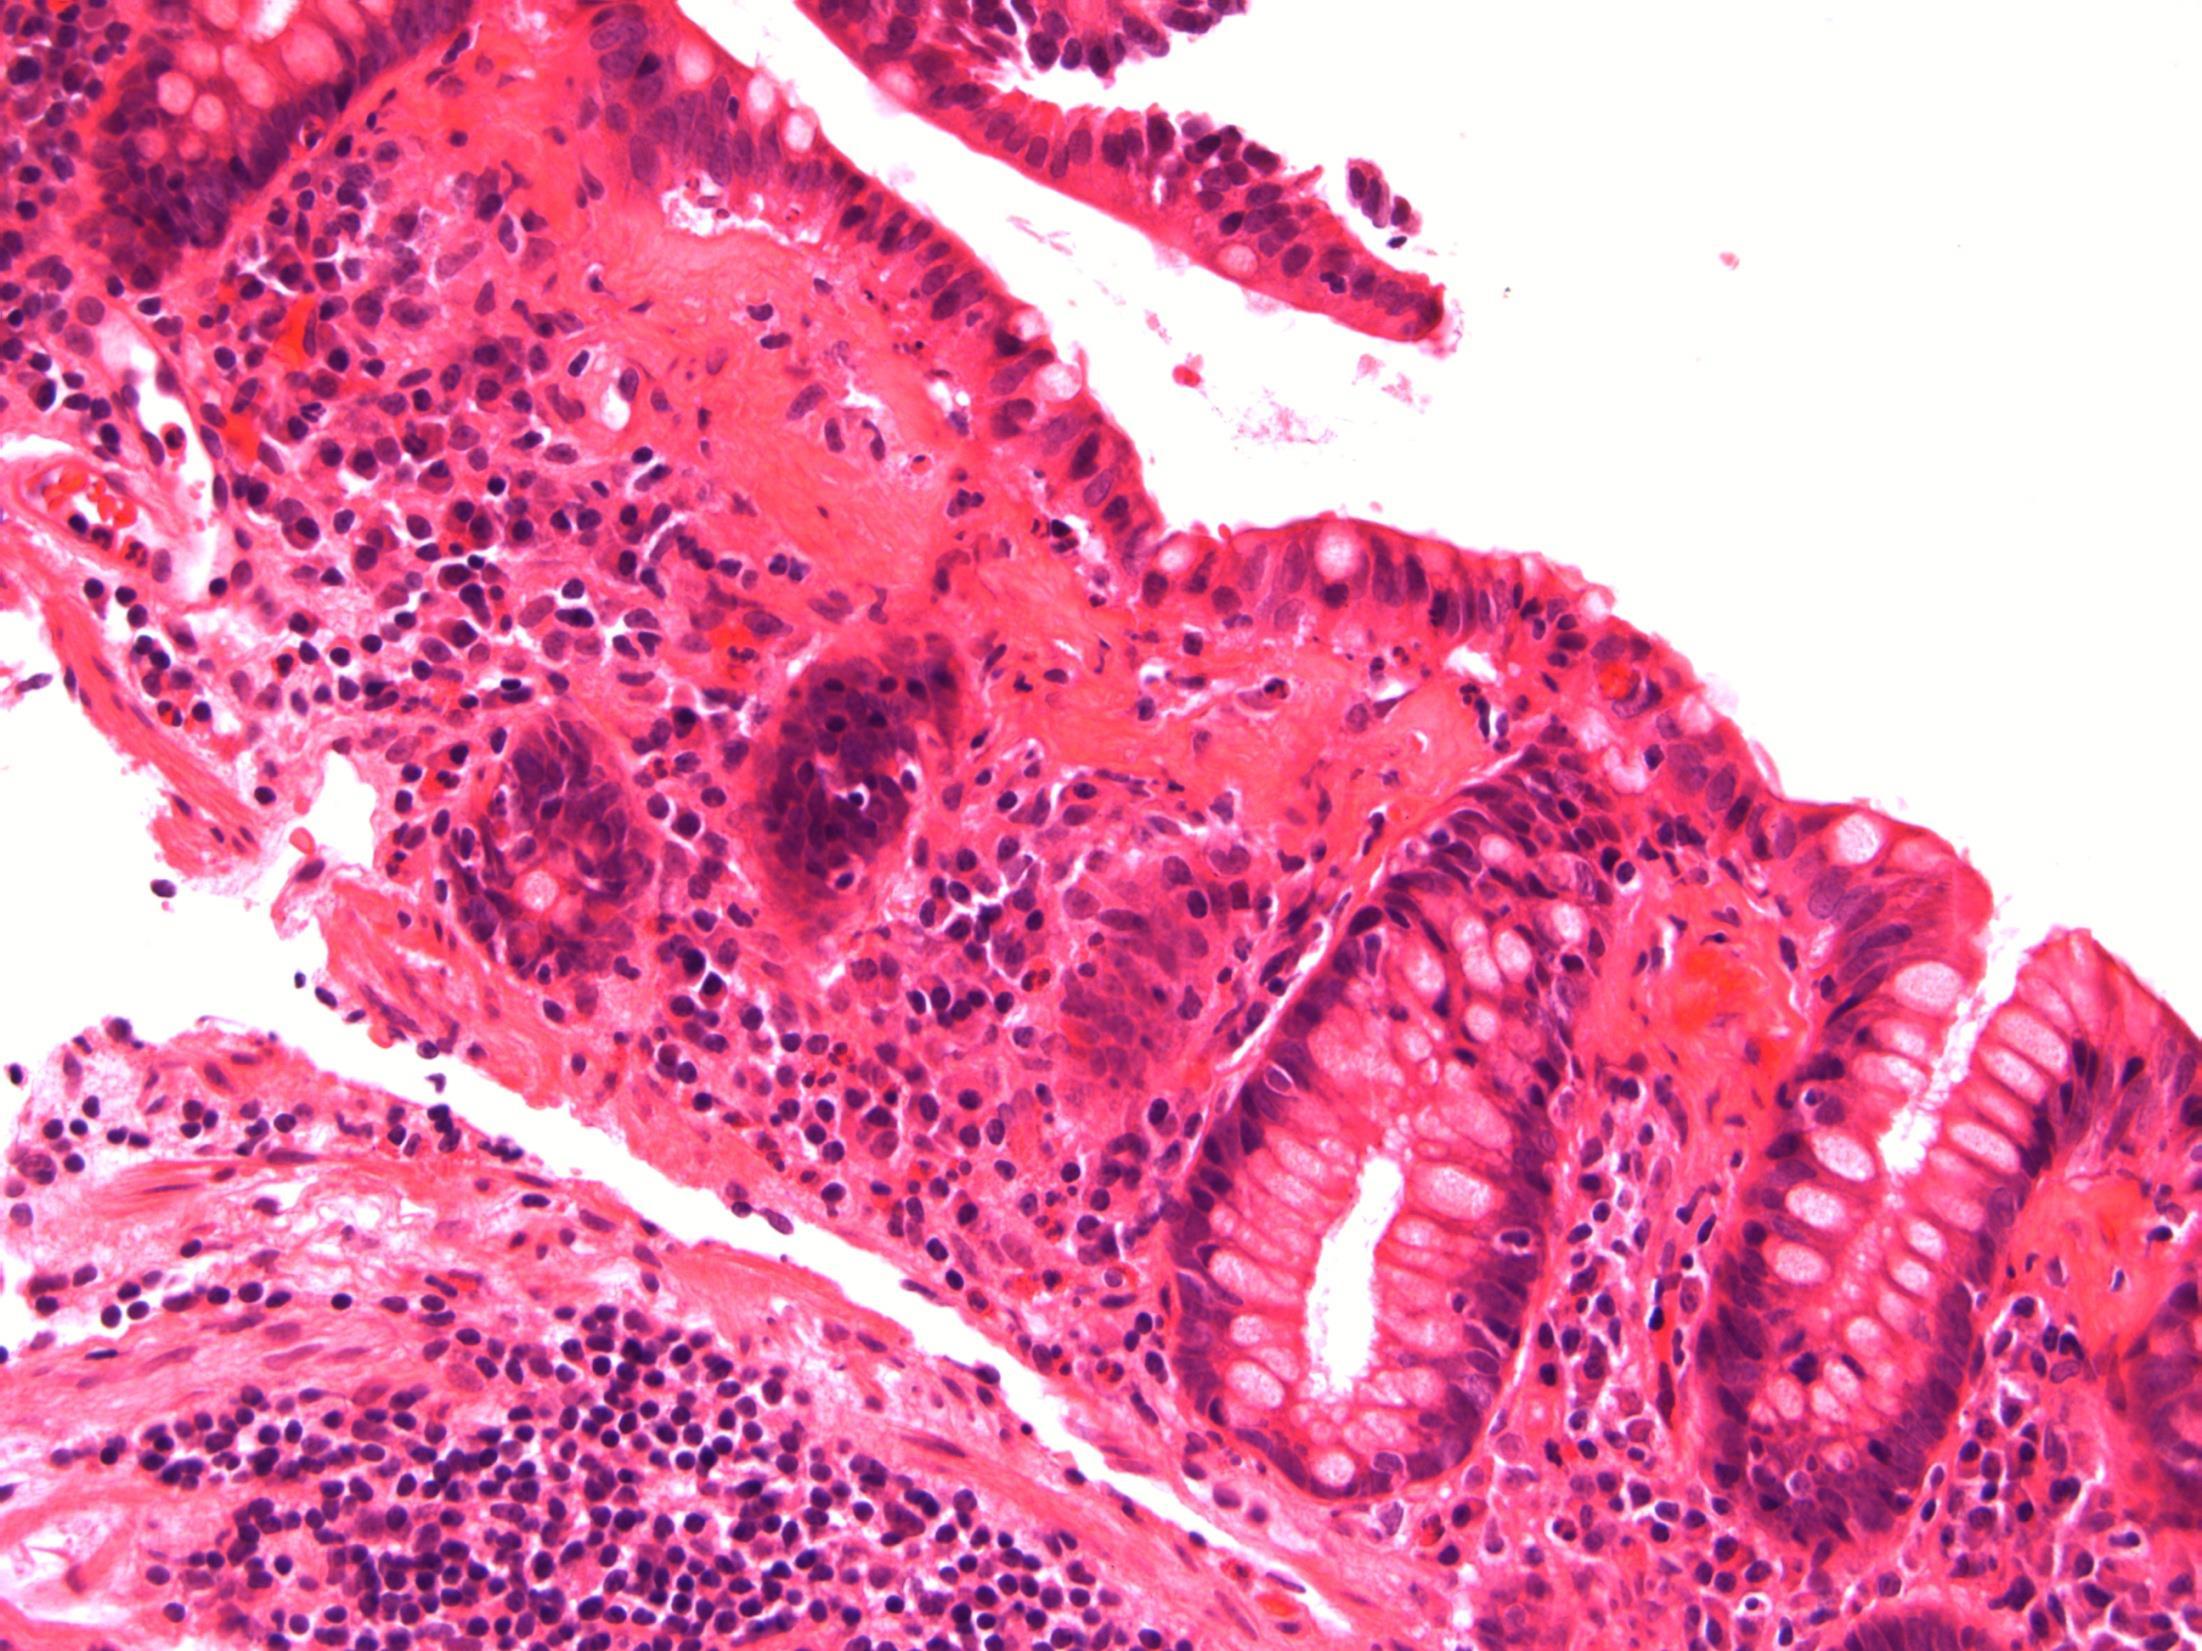

Pseudomembranous colitis

• Description: Patchy necrosis of mucosa, with mushroom shaped fibrinopurulent exudates on surface, crypt withering, hyalinisation of lamina propria

• Diagnosis: Pseudomembranous colitis

Differential diagnosis: Acute ischaemic colitis (can be very difficult – a lot depends on the history and clinical context, but usually more localised / segmental and full thickness necrosis)

• Plan: Correlate with microbiology, antibiotic history, endoscopy etc

• Comments: PMC typically follows antibiotic administration, which correlates well with the history provided. Caused due to toxins of C. difficile